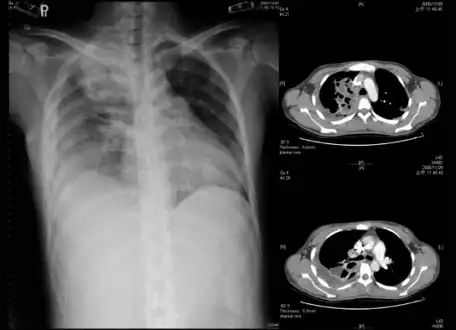

Lungs

Empyema

Empyema with abscess